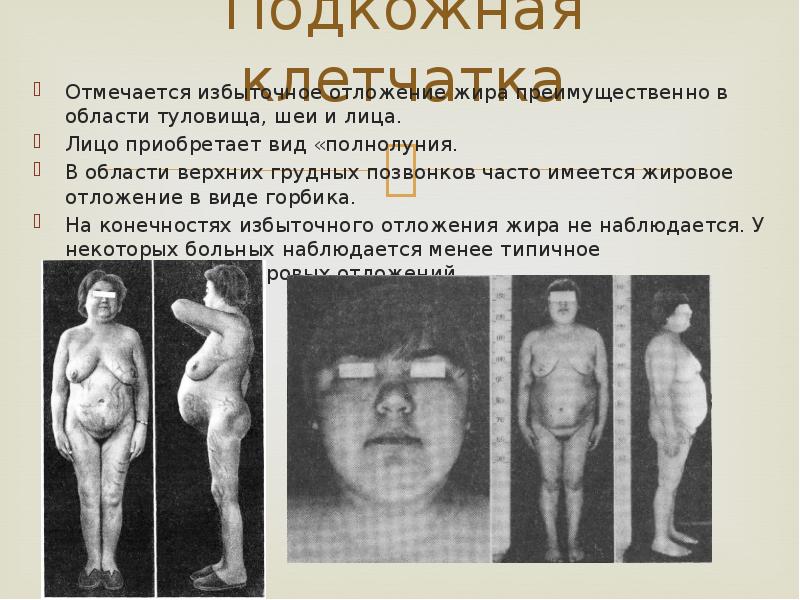

Подкожная клетчатка

Отмечается избыточное отложение жира преимущественно в области туловища, шеи и лица.

Лицо приобретает вид «полнолуния.

В области верхних грудных позвонков часто имеется жировое отложение в виде горбика.

На конечностях избыточного отложения жира не наблюдается. У некоторых больных наблюдается менее типичное распределение жировых отложений.